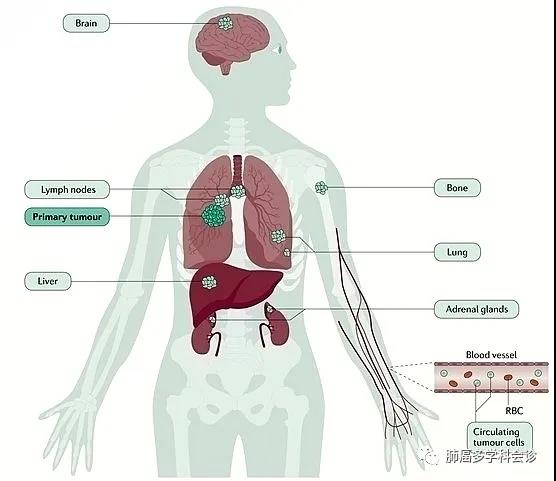

福建省肿瘤医院始终扮演着我省抗癌工作的坚强堡垒角色,并为肿瘤病人提供综合治疗,兜底全省的疑难重症癌症病人诊治工作。近年,医院强化技术创新,建立了各种肿瘤多学科诊疗的技术体系和全疾病周期的健康管理,针对每个病人的不同病情制定个体化诊疗策略,有机地在病人的不同治疗阶段合理使用,最大程度提高远期疗效,同时保障病人的生活质量,延长晚期病人生存期,使更多不可治的肿瘤得到可治。初步统计,2022年相关数据显示,在外院抗肿瘤治疗后转诊至该院进一步治疗的疑难病人治愈及好转率达 45.85%,有效率 96.5%。 当前,全院上下正坚持用党的创新理论武装头脑、指导实践、推动工作,坚持学理论、悟思想,边学习边思考,边检视边整改,切实推动党建和业务工作双融双促,努力在以学铸魂、以学增智、以学正风、以学促干上取得实效。 近期,海都记者走访了省肿瘤医院,通过一个个生动的事例,展现该院是如何让“不可治”的肿瘤变得“可治”。 五十多岁的李先生是一名EGFR突变晚期肺癌患者,经化疗、免疫治疗后,病灶仍增大,且肿瘤对三代EGFR-TKIs产生耐药。一时间乌云笼罩,治疗陷入僵局。 福建省肿瘤医院胸部肿瘤内科何志勇主任团队,针对李先生的情况仔细研究、探讨后,制定了提高三代EGFR-TKI的给药浓度的方案,最终取得令人欣喜的结果,肿瘤明显退缩。目前,李先生仍在维持治疗中,病情稳定,生活质量良好。 据悉,几乎每个EGFR突变晚期肺癌患者都要面临耐药的问题,这类患者的治疗也是目前临床上的难点和热点。福建省肿瘤医院胸部肿瘤内科何志勇主任团队一直在探索研究。 时间拉回到三年前。2019年12月,五十多岁的莆田患者李先生来到福建省肿瘤医院胸部肿瘤内科何志勇主任门诊,他患有EGFR突变晚期肺癌,且往已经接受过多种方案治疗,包括化疗、一代EGFR-TKI治疗24个月、三代EGFR-TKI治疗18个月。 “当时,患者肺部病灶增大,提示肿瘤对三代EGFR-TKI耐药,因仅肺部肿瘤增大,我们建议继续三代EGFR-TKI联合抗血管靶向治疗,患者仍有获益,无进展生存时间9个月。” 何志勇主任介绍说,后来,李先生仍由于肺部病灶的进展接受过多程的化疗联合免疫治疗,期间肺部肿瘤进展缓慢,直至2022年9月,肿瘤又出现快速进展,表现为双肺转移灶增大增多、并新增多发肝转移。 双肺转移灶增大增多,并新增多发肝转移男子接受了多方案治疗肺癌仍在增大并转移

18例控制率86%

近年来,何志勇主任团队在双倍剂量伏美替尼治疗三代EGFR-TKI耐药的临床实践中,做了临床层面的探索,并总结了临床经验。近2年来,团队共应用双倍剂量伏美替尼18例,其中,3例是初治脑转移患者,15例是三代EGFR-TKI耐药且经历多线治疗后的患者,治疗都能达到不同程度的肿瘤缩小,总体缓解率为86%(13/15),中位疾病缓解时间为4个月,最长的超过17个月。

另据介绍,三代EGFR-TKI耐药后肺癌患者的治疗,是目前临床上的难点和热点。近年来,何志勇主任团队致力于在临床中探索不同的行之有效的策略。除了双倍剂量伏美替尼,团队还采用节拍治疗克服三代EGFR-TKI耐药,总结了28例患者的临床数据,疾病控制率达到89.3%